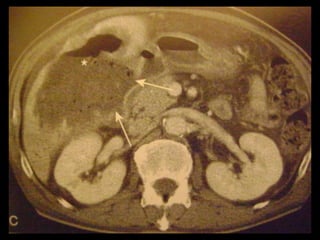

Perfuração

Achados na TC

1. Interrupção da parede da vesícula biliar ou a

presença de um defeito focal;

2. Pode-se observar um cálculo fora do lúmen da

VB;

3. Formação de abscesso perivesicular restrita à

fossa.

A TC auxilia na avaliação complementar e na

determinação mais precisa da extensão da

inflamação

Perfuração Achados na TC 1. Interrupção da parede da vesícula biliar ou a presença de um defeito focal; 2. Pode-se observar um cálculo fora do lúmen da VB; 3. Formação de abscesso perivesicular restrita à fossa. A TC auxilia na avaliação complementar e na determinação mais precisa da extensão da inflamação